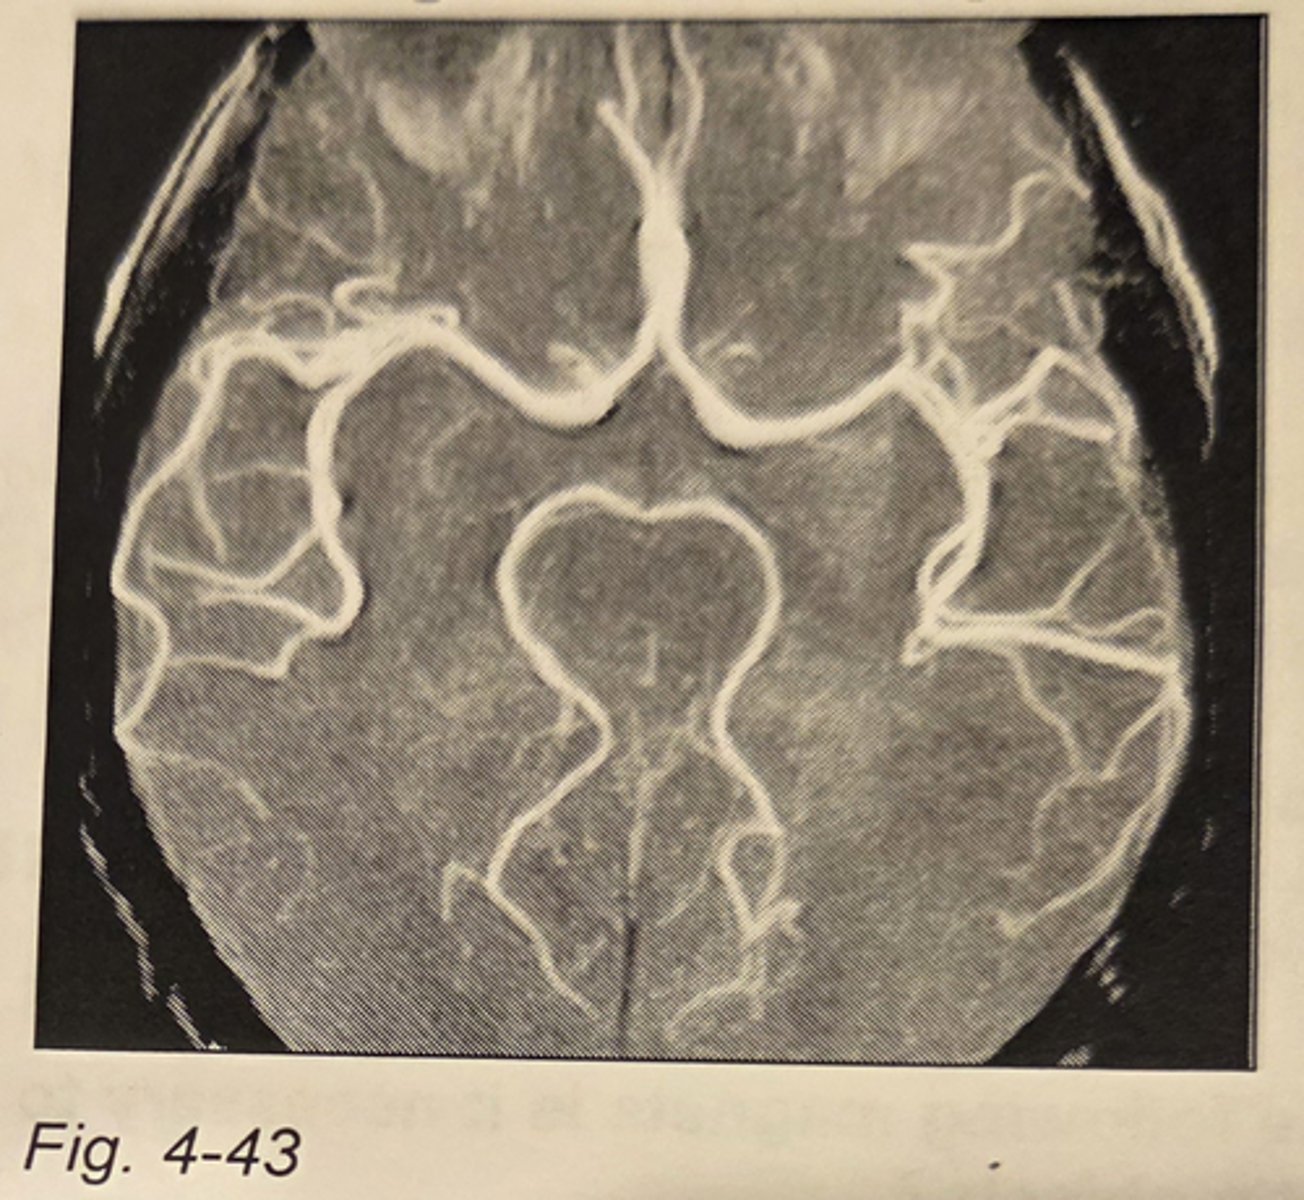

Which of the following types of sequences was most likely used to generate the image in Fig. 4-43?

gradient echo